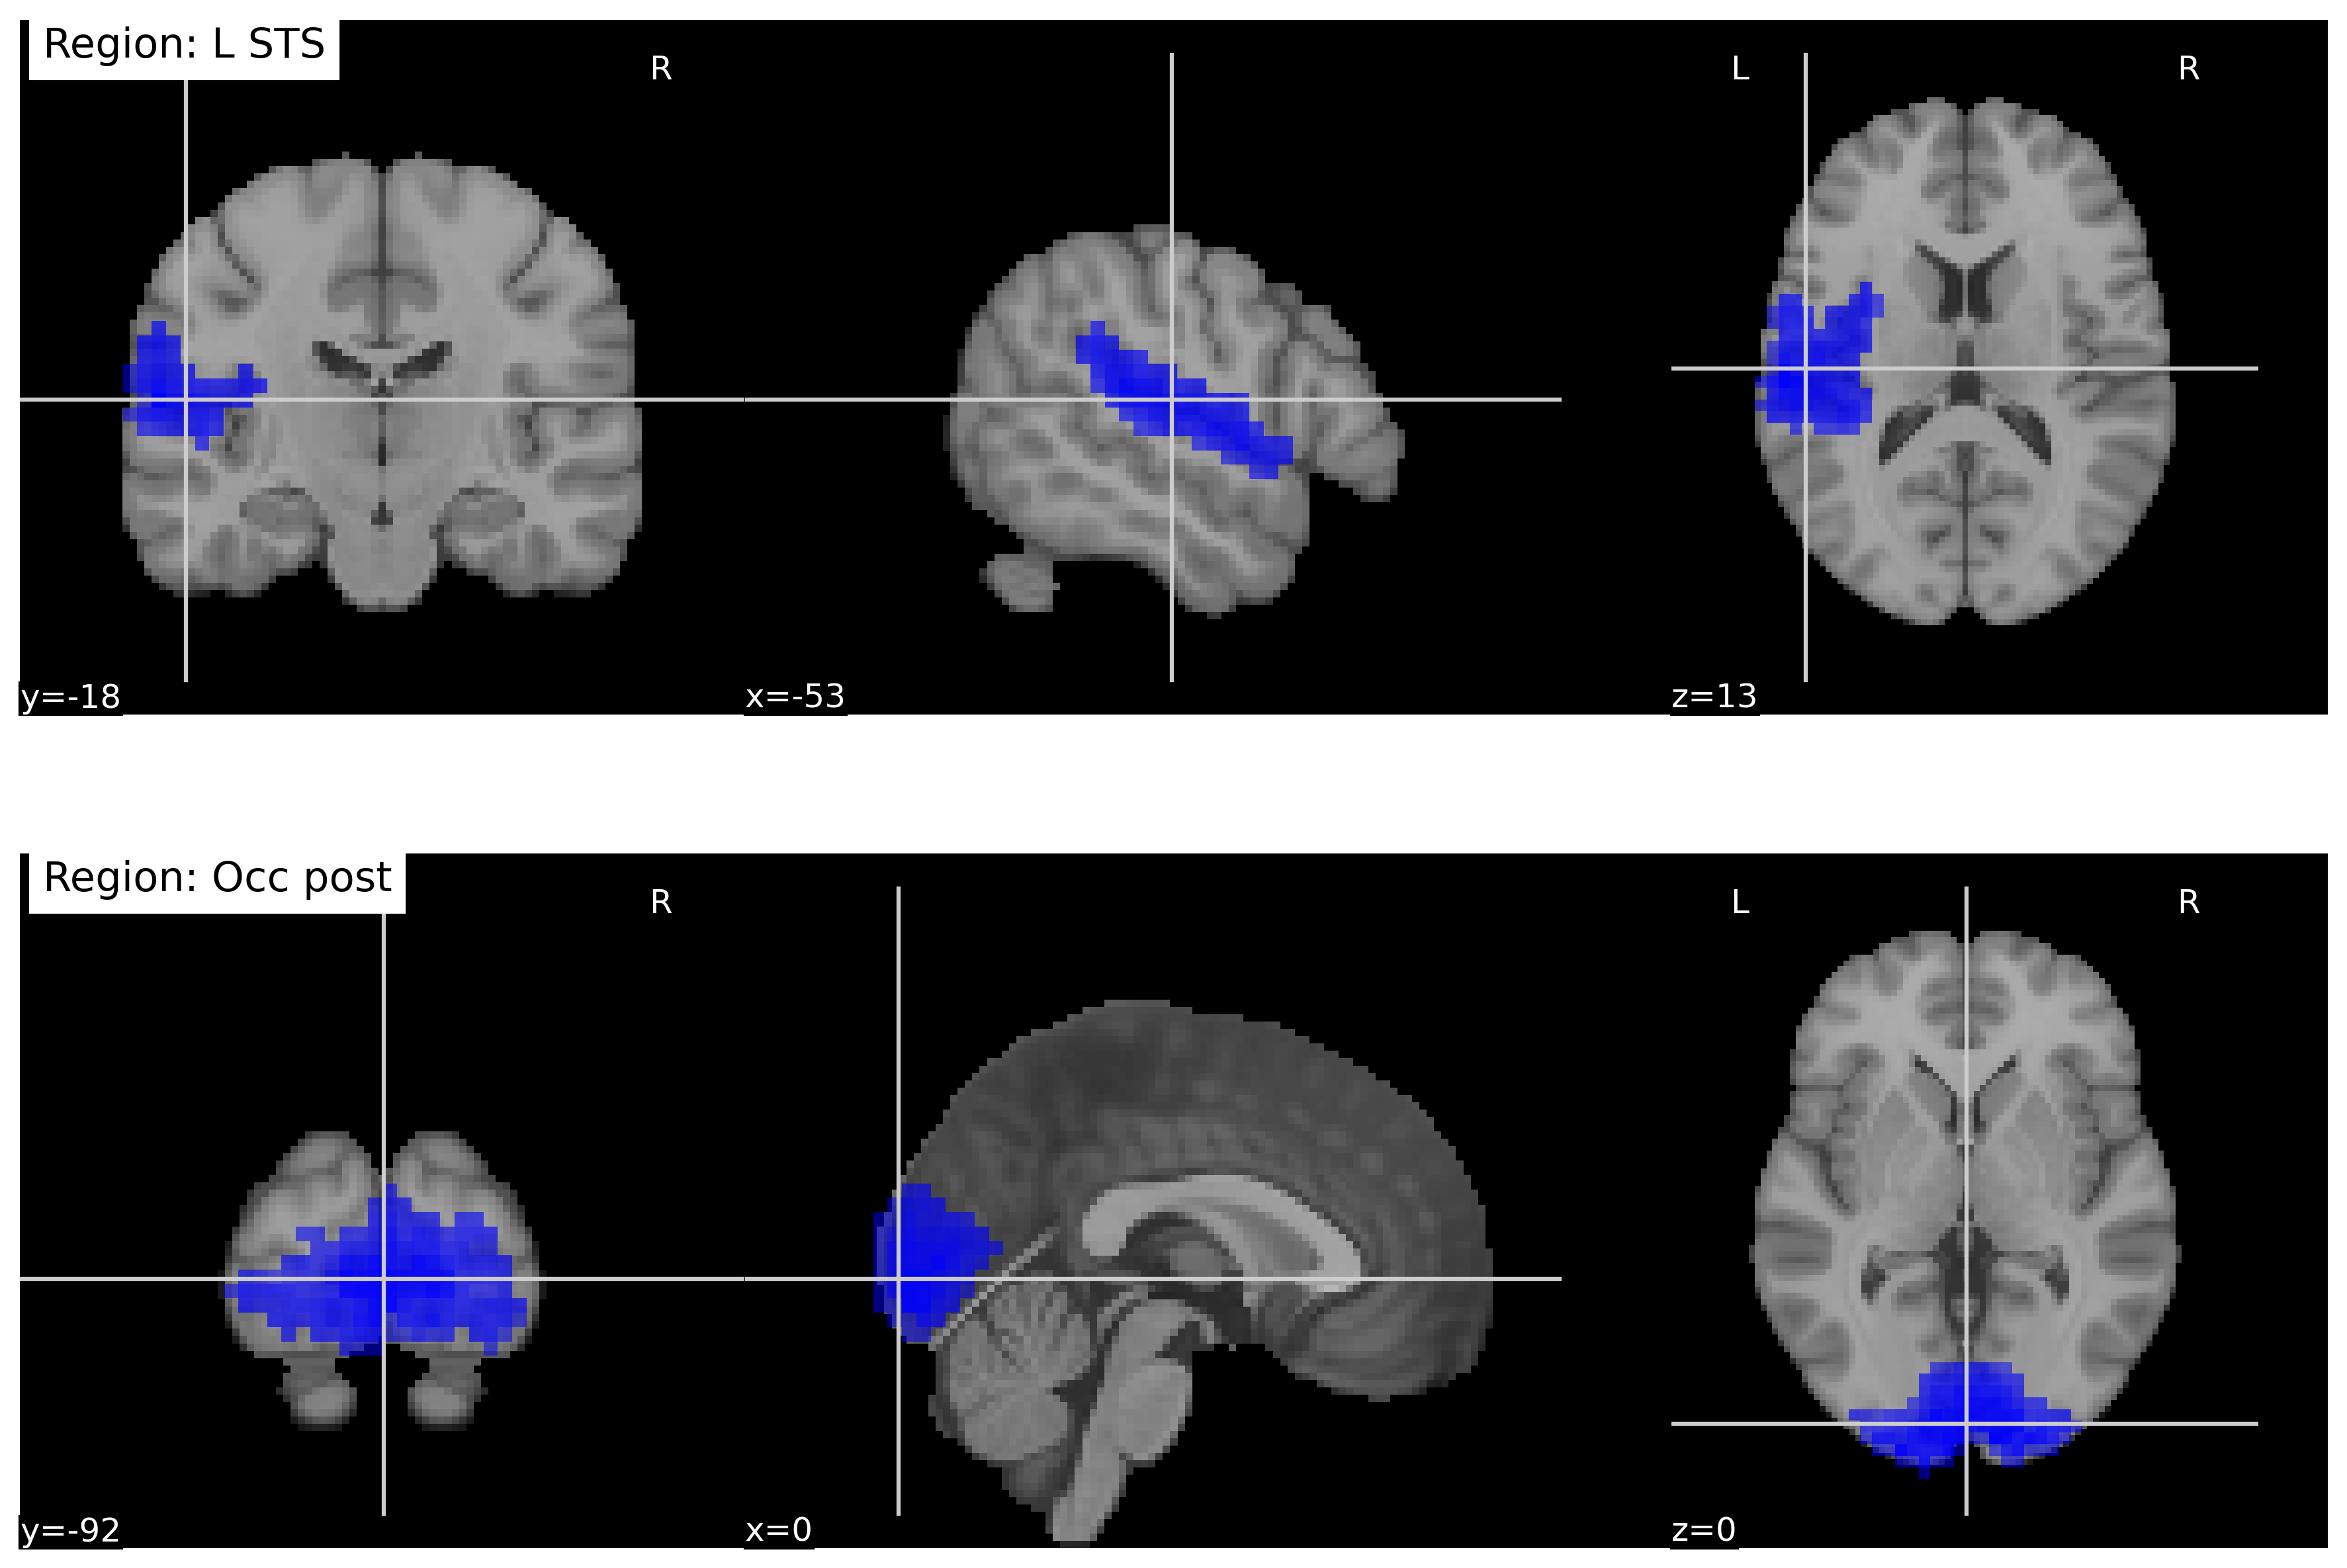

The learned regional saliency and connectivity patterns provide insight into the neurobiological mechanisms captured by the proposed model. Overall, the extracted features are consistent with known alterations in sensory, temporal, and associative brain systems in ASD [4]. Fig. 4 shows that the model assigns high importance to the left superior temporal sulcus (STS) and posterior occipital cortex, regions involved in social perception, language, and audiovisual integration. Atypical structure and function of the STS and posterior temporal–occipital regions have been widely reported in ASD and are closely linked to deficits in social communication and sensory processing [29].

Figure 4: Regional brain activations based on NeuroMambaLLM Results. Prominent involvement of the left superior temporal sulcus (STS) and posterior occipital regions highlights circuits related to social perception/audiovisual integration and early visual-sensory processing.